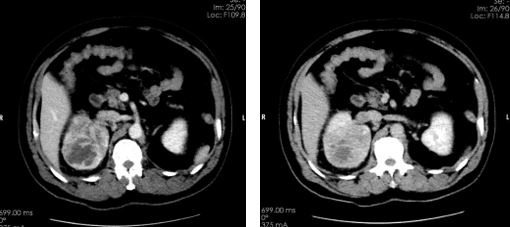

临床资料: 男性,65岁,血尿3天就诊。 扫描方法: 常规GSI平扫+增强,对比剂碘海醇(350mgI/100ml)80ml,3ml/s。 CT印象:

平扫右肾上极低密度肿块影

动脉期肿块明显增强

分泌期及排泄期肿块内对比剂廓清,呈典型快进快出表现

右肺结节能谱曲线与右肾上极肿块完全重合(图示为黄色和红色曲线) 临床分析与诊断: 该患者右肾肿瘤是典型的透明细胞癌表现,右肺孤立结节通过能谱曲线分析,两者完全重合,诊断为右肾透明细胞癌并右肺下叶转移瘤。 右肾肿瘤后经术后病理证实为肾透明细胞癌,右肺结节亦经随访证实,说明CT的临床诊断准确清楚。 病例小结: 能谱四大工具之一的能谱曲线,可以通过比较两者曲线的斜率及走行对疑似转移病灶进行更进一步的分析,以明确是否同一来源抑或是不同性质的病变,可为临床提供更准确的判断和更多有价值的信息,从而达到诊断及鉴别诊断的目的。 临床小知识: 肾透明细胞癌来源于肾小管上皮细胞的腺癌,癌中常有出血、坏死、囊变和钙化。生于肾实质内,长大后浸润、压迫、破坏肾盂肾盏,向肾包膜外发展,形成血管瘤栓或转移到淋巴结及其他脏器。肾透明细胞癌早期常无症状,或症状较隐匿。可能有轻微的发热、乏力等全身症状,肿瘤体积增大时才被发现。临床主要表现为血尿、肾区疼痛和肿块等。 病例来源:聊城市第三人民医院